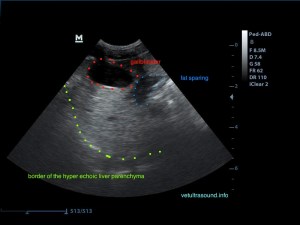

Το fat sparing είναι μία έκφραση που χρησιμοποιείται κατά την υπερηχοτομογραφική εξέταση, σε περιπτώσεις λιποείδωσης του ήπατος για να περιγράψει περιοχές του ηπατικού παρεγχύματος στο οποίο δεν έχει γίνει εναπόθεση λίπους. Πολλές φορές μπορεί η λιποείδωση να είναι σε τέτοιο βαθμό ώστε όλο το ήπαρ να είναι ομοιόμορφα υπερηχογενές και να εντοπίζονται εστιακές ή πολυεστιακές περιοχές υποηχογένειας και η διαφοροποίηση του ποιά από τις δύο απεικονίσεις είναι φυσιολογική να είναι δύσκολη. Αυτή η εικόνα μπορεί να επηρεάσει και την εκλογή του σημείου που θα πρέπει να γίνει βιοψία ή FNA.

Το ήπαρ εμφανίζεται υπερηχογενές και ο ήχος εξαντλείται καθώς περνάει μέσα από αυτό. Δεν είναι εύκολη η διαφοροποίηση του τοιχώματος της πυλαίας φλέβας σε σχέση με το υπόλοιπο παρέγχυμα.

Αντίθετα στο τμήμα που δεν έχει γίνει εναπόθεση λίπους είναι εύκολη η απεικόνιση του τοιχώματος της πυλαίας φλέβας.

Δεν προκαλεί συμπίεση των γύρω ιστών ή αγγείων (mass effect) το υγιές τμήμα του ηπατικού παρεγχύματος.